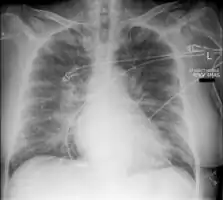

| Pulmonary edema with small pleural effusions on both sides. | |

Low oxygen saturation and disturbed arterial blood gas readings support the proposed diagnosis by suggesting a pulmonary shunt. A chest X-ray will show fluid in the alveolar walls, Kerley B lines, increased vascular shadowing in a classical batwing peri-hilum pattern, upper lobe diversion (increased blood flow to the superior parts of the lung), and possibly pleural effusions. In contrast, patchy alveolar infiltrates are more typically associated with noncardiogenic edema[8]